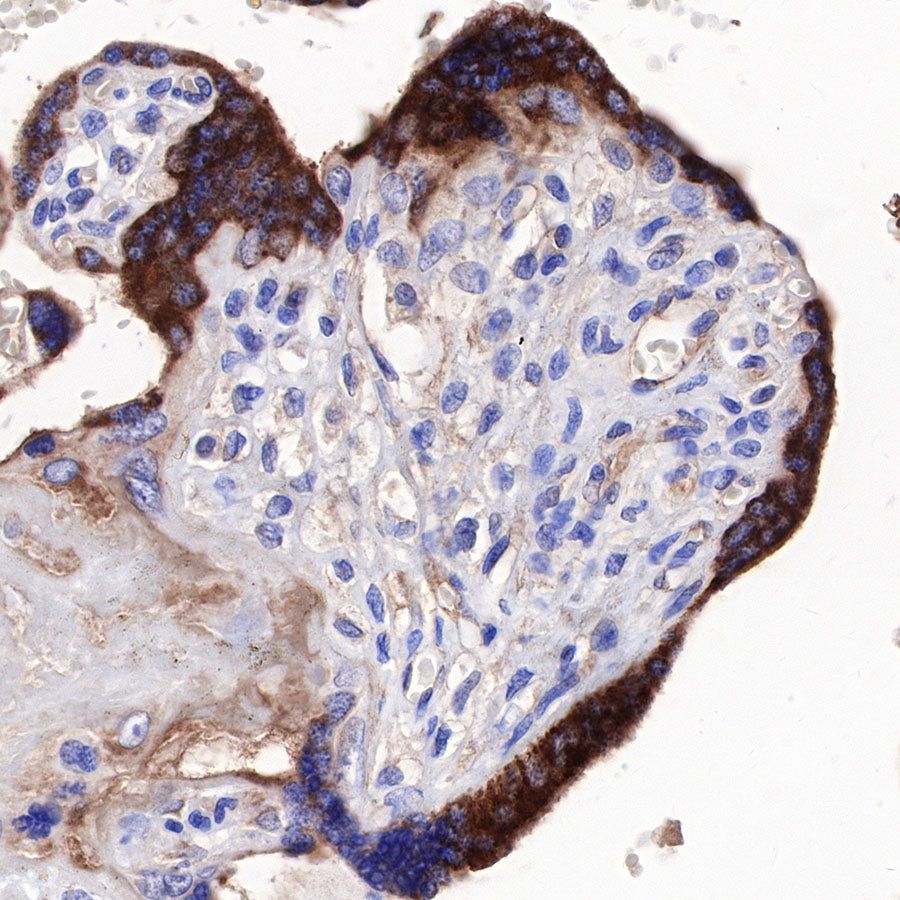

IHC shows positive staining in paraffin-embedded human endometrial cancer. Anti-sFlt-1/VEGF Receptor 1 antibody was used at 1/1000 dilution, followed by a HRP Polymer for Mouse & Rabbit IgG (ready to use). Counterstained with hematoxylin. Heat mediated antigen retrieval with Tris/EDTA buffer pH9.0 was performed before commencing with IHC staining protocol.